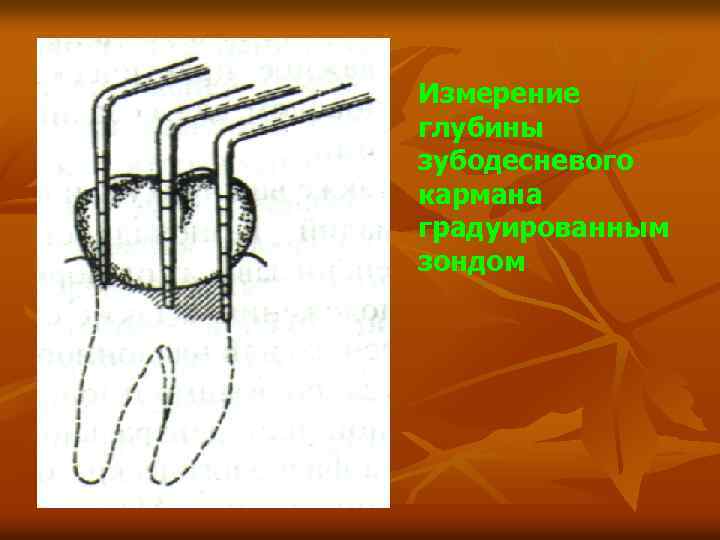

Пародонтометр Sheuermann Пародонтометр Hauer

Измерение глубины зубодесневого кармана градуированным зондом

Расположение инструмента по отношению к зубу правильно неправильно